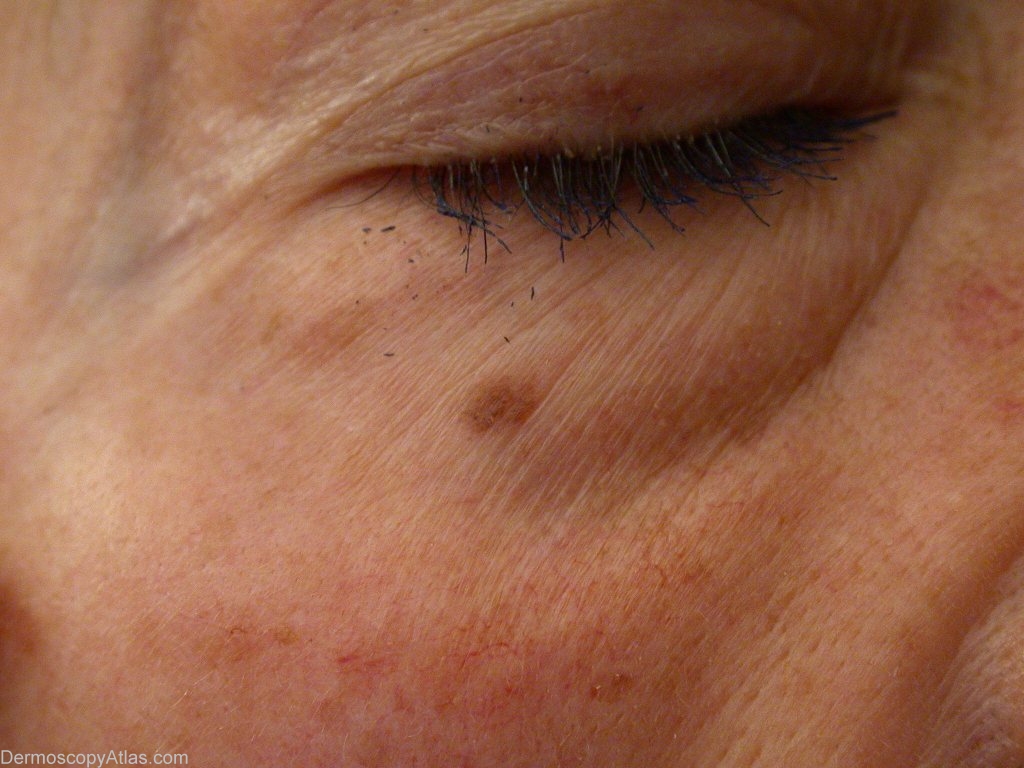

Site: Eyelids

Description: Dark spot of the eye lid.

History: This lady came for the removal of dark spots on her face. Most of them were solar lentigos. One one them, right eyelid, had a suspect dermoscopic image. Excision followed by pathology revealed a small lentigo maligna.